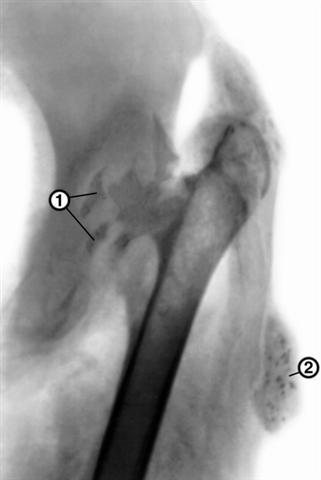

Рис. 5. Рентгенограмма левого тазобедренного сустава (переднезадняя проекция) при туберкулезном коксите в постартритической фазе: головка бедренной кости полностью разрушена, шейка бедренной кости истончена и склерозирована, вертлужная впадина расширена за счет деструкции ее свода, видны секвестры (1), в наружных отделах мягких тканей бедра — натечный абсцесс (2). |